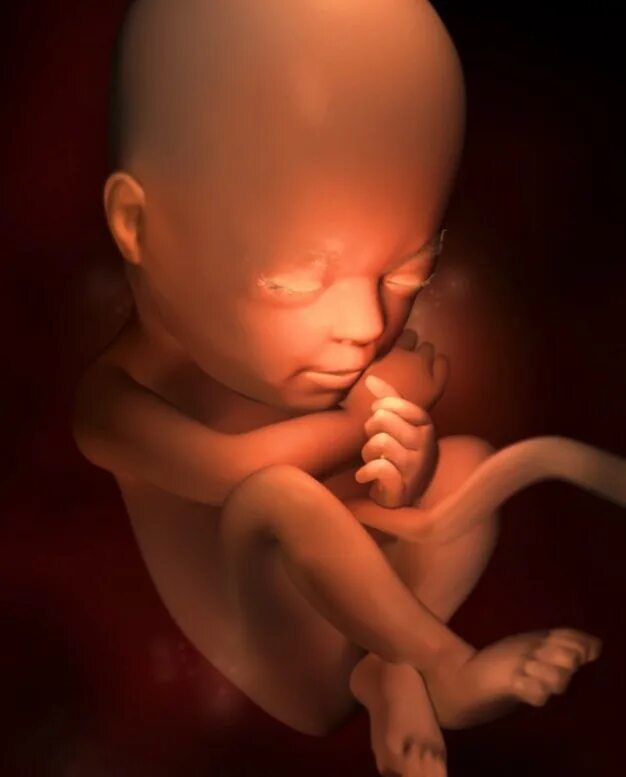

Как выглядит ребенок в 22 недели